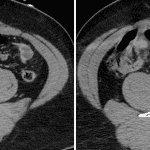

- Acute, comminuted, minimally displaced right sacral fracture with involvement of the S3 and S4 neural foramina

- Adjacent small right piriformis intramuscular hematoma with a small focus of contrast density which increases in size on delayed images

Right sacral fracture involving the right S3 and S4 neural foramina with an adjacent right piriformis intramuscular hematoma and small area of active hemorrhage.